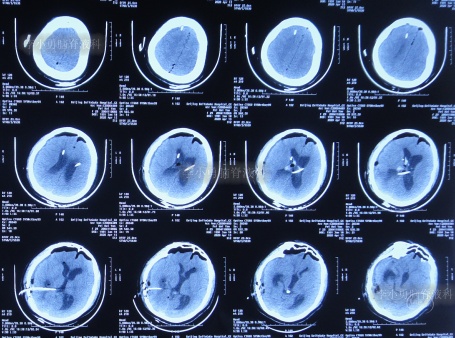

于入院后2019年12月30日,进行了第3次进行了脑室腹腔分流术(分流阀初始压力2.0),仍保留了原2根脑室分流管;术后当天查头颅CT示脑室仍有扩张,脑室内有3根管(图-9)。

图-9:2019年12月30日头颅CT

第3次脑室腹腔分流术后1个月即2020年2月初,再次出现记忆力减退视物模糊,再过1个月仍无任何改善,于2020年3月17日(第3次脑室腹腔分流术后2个半月),到江苏省江阴某医院检查了头颅CT示脑室仍扩张(图-10)。

图-10:2020年3月17日头颅CT

2020年4月5日(第1次调压后18天),因症状持续不见减轻,到江苏省江阴某医院查头颅CT示脑室仍扩张(图-11)。

图-11:2020年4月5日头颅CT

但第2次调压仅2天后,症状又加重,到江苏省江阴某医院查头颅CT示脑室仍扩张(图-12)。为求进一步有效治疗,通过网络找到北京的李小勇脑脊液科。

图-12:2020年4月9日头颅CT

脑积水第1次脑室腹腔分流术后14年,即第2次脑室腹腔分流术后13年,即第3次脑室腹腔分流术后3个月半,5次就诊于给予手术的医院但仍脑积水,颅内感染情况下于2020年4月11日,住入李小勇脑脊液科,入院时:头晕伴视物不清,呕吐,睡眠差,头部有手术瘢痕(图-13);入院时头颅CT示脑积水,脑室内有3根管(图-14)。

图-14:2020年4月11日入院时头颅CT